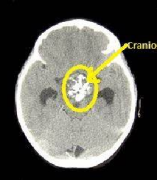

颅咽管瘤属于良性胚胎源发性肿瘤根据世界卫生组织(WHO)分类标准其起源于Rathke囊的鳞状上皮残余组织;因此,该肿瘤可出现在其迁移路径的任何节段,...

颅咽管瘤是一种来源于胚胎残余组织的良性肿瘤,颅咽管瘤约占儿童全部脑瘤的6%。任何年龄的人都有可能被诊断为颅咽管瘤,但在5到14岁之间较容易被诊...

颅咽管瘤 是起源于神经上皮的肿瘤,由鳞状细胞沿原颅咽管道长出。它们的发病率在每10万人年0.5至2.5之间,不因性别或种族而有所不同。颅咽管瘤占全部...